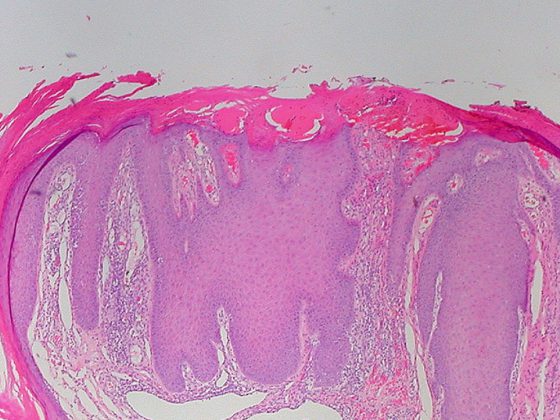

prurigo_nodularis_5078047877

Chronische Prurigo bei atopischen Patienten: erfolgreiche Behandlung mit Dupilumab